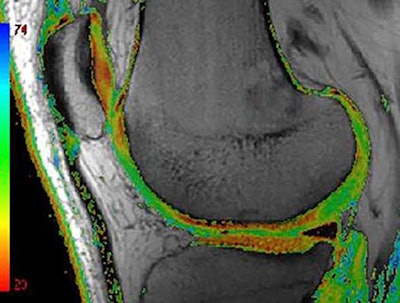

For quantitative and qualitative analyses using MRI, Roemer finds 3D morphometry particularly valuable.

"This is based on tissue segmentation and is being widely used for cartilage quantification," he said. "The cartilage tissue is well contrasted between the intra-articular fluid and the subchondral bone. Regions of interests are drawn around the cartilage, and multiple parameters can be extracted from those 3D segmentations, including cartilage volume, cartilage thickness, the amount of the denoted bone area beneath the cartilage, and so on."

Compositional MRI techniques, including T2 mapping or T2 relaxometry, can be used to look at the ultrastructure of tissue. Basically, the different analytical approaches are semiquantitative, quantitative, and qualitative compositional measures of tissue change, Roemer noted.